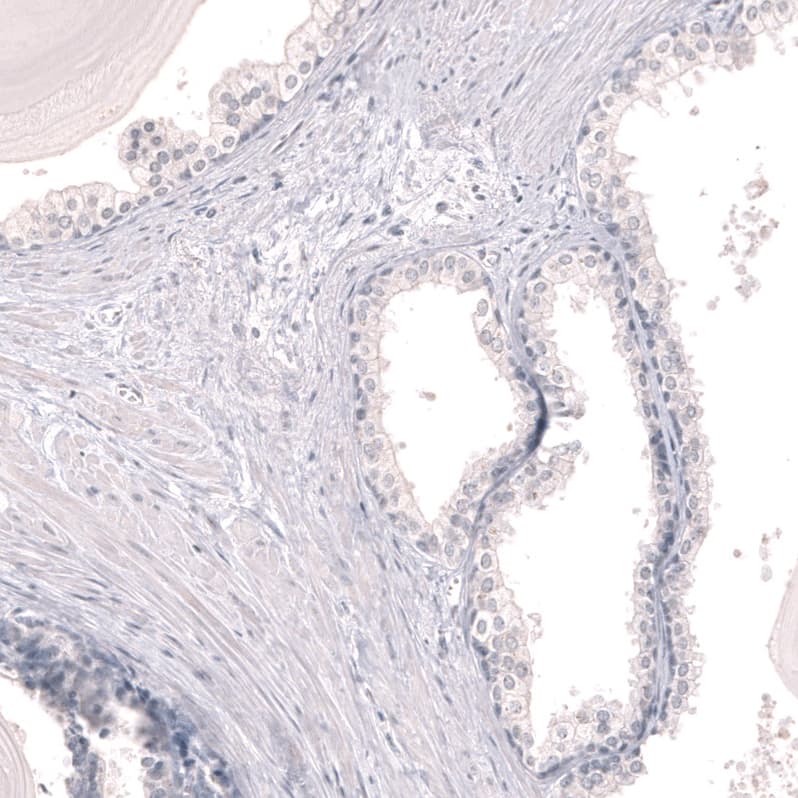

Staining of human prostate shows no positivity in glandular cells as expected.